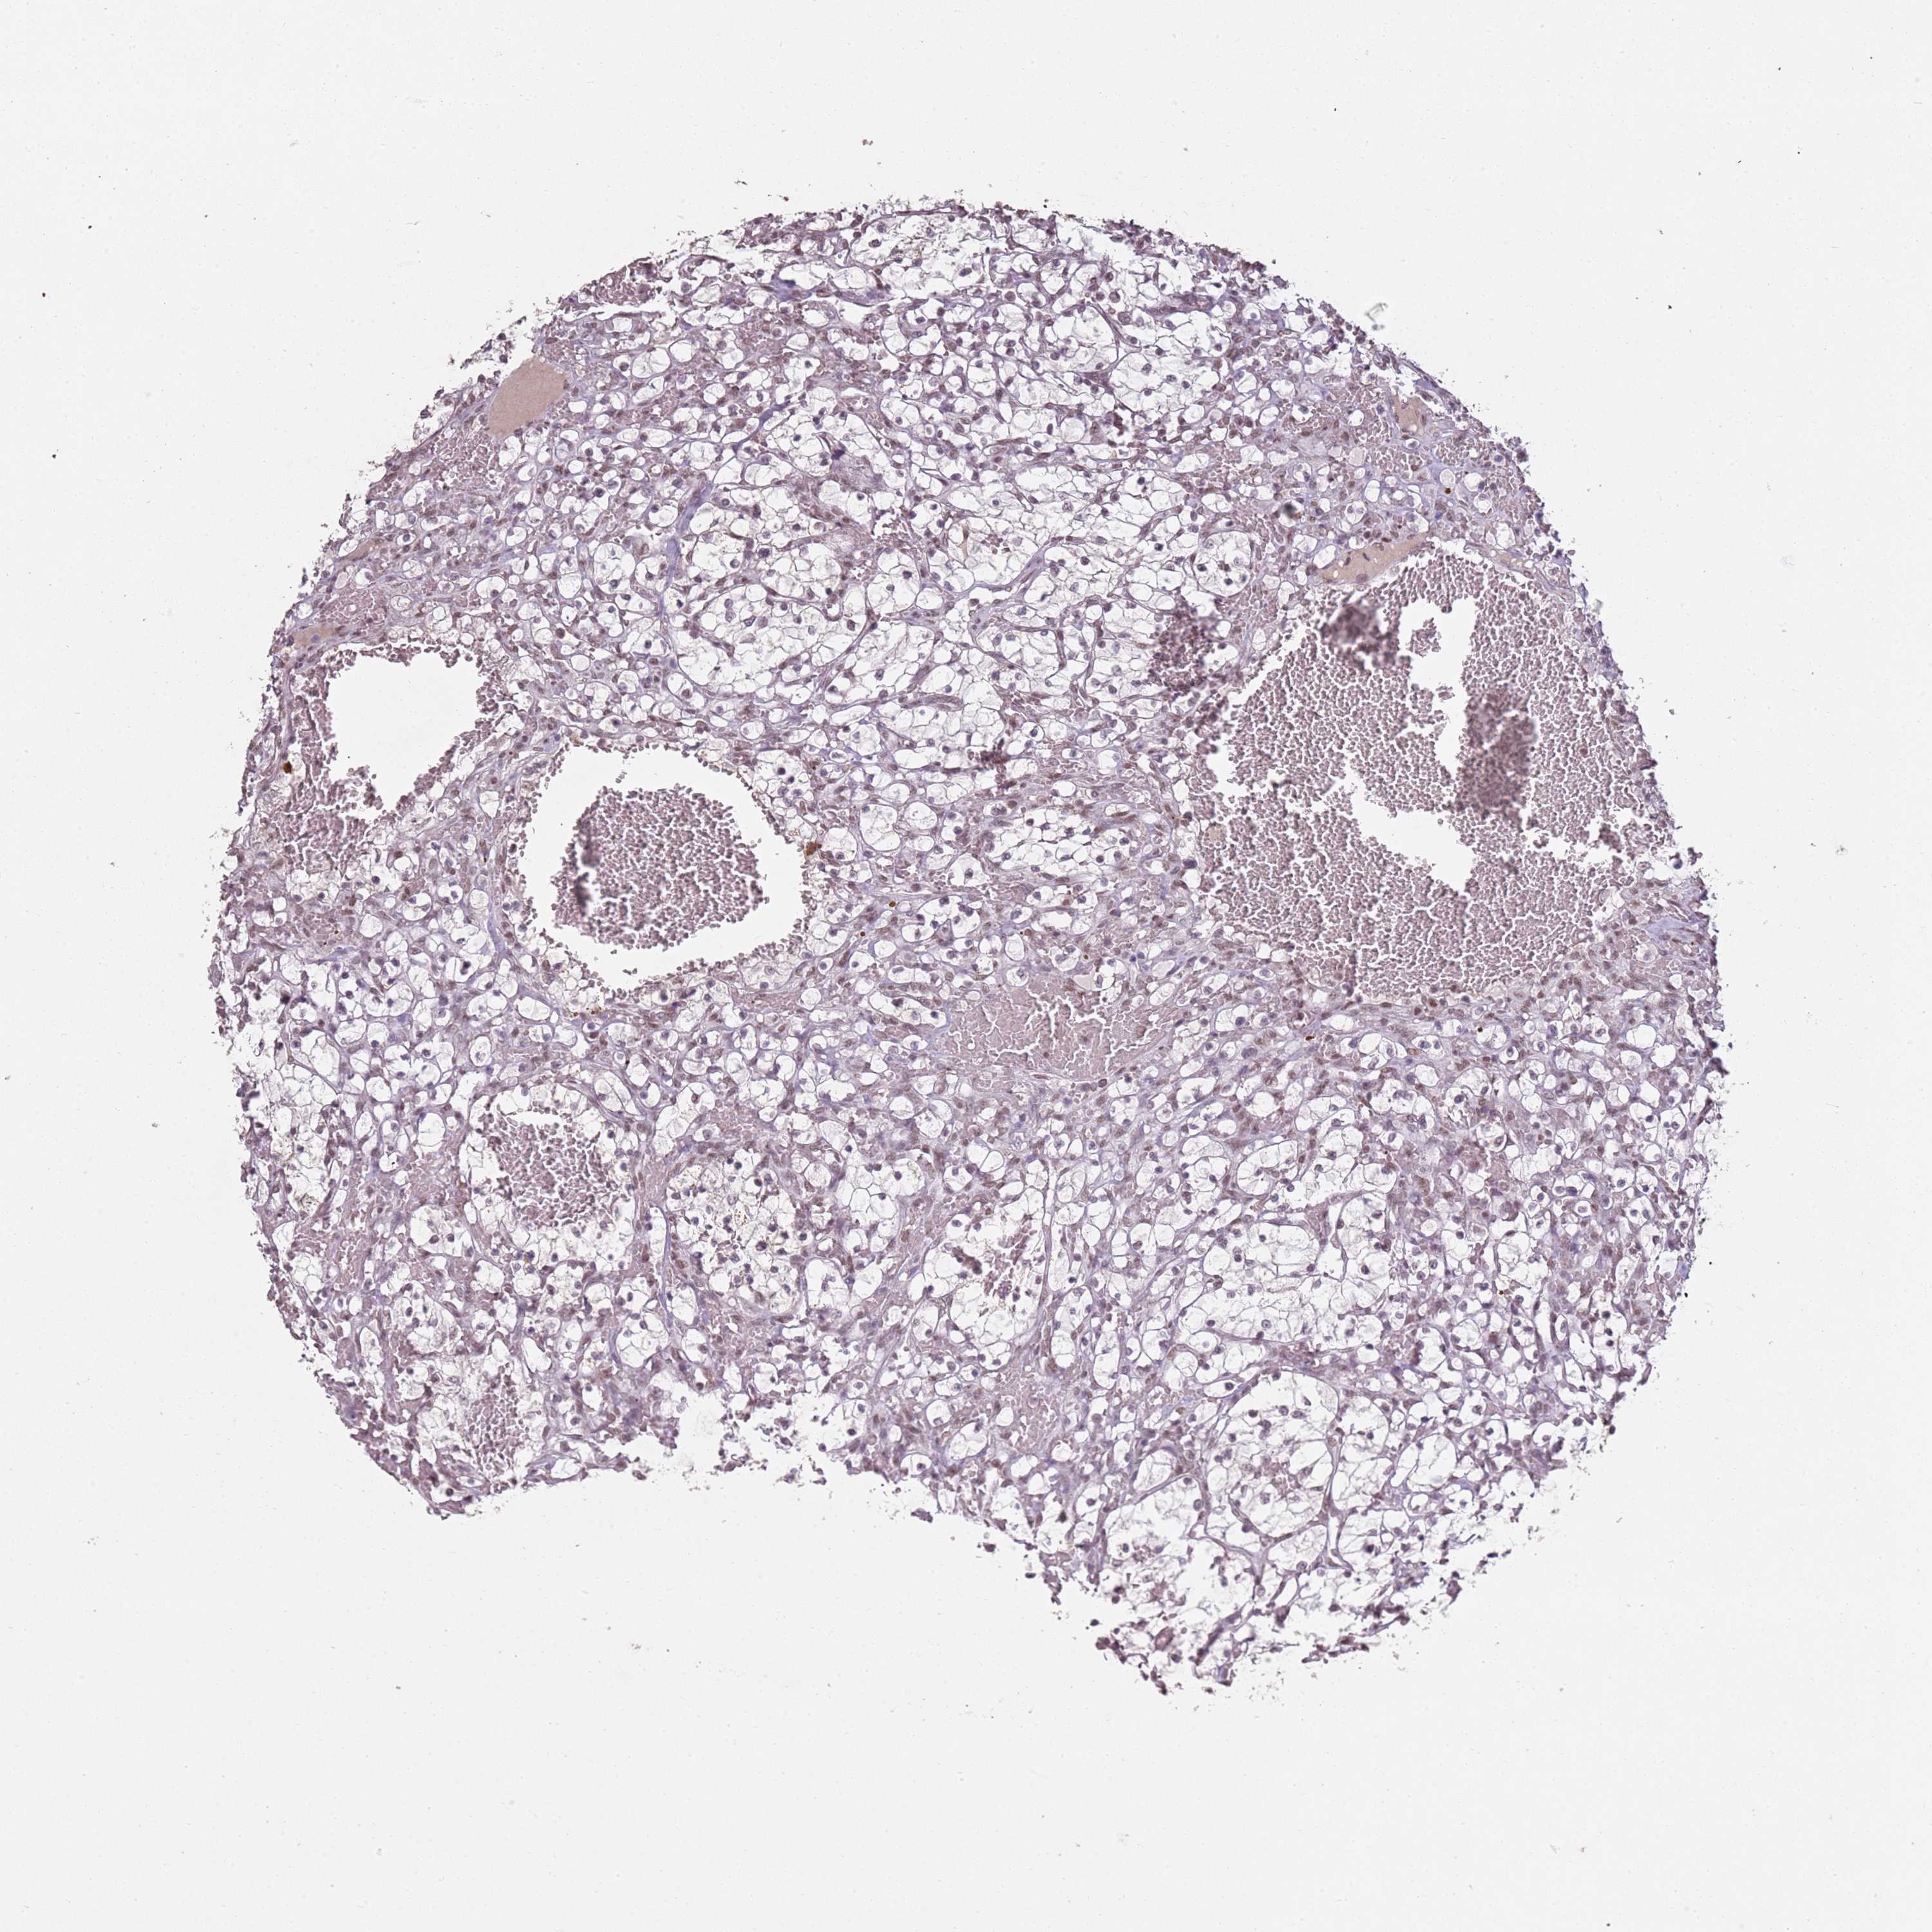

ARL14EP is not prognostic in Kidney Renal Papillary Cell Carcinoma (TCGA)

Best expression cut offi

When clicking on this number, the vertical dashed line indicating cut-off, the interactive survival plot, and the Kaplan-Meier curve will be adjusted to show results based on the best expression cut-off.

: 11.08

: N/A

Log-rank P value for Kaplan-Meier plot showing results from analysis of correlation between mRNA expression level and patient survival.

N/A

For melanoma and glioma, 3-year survival is shown.